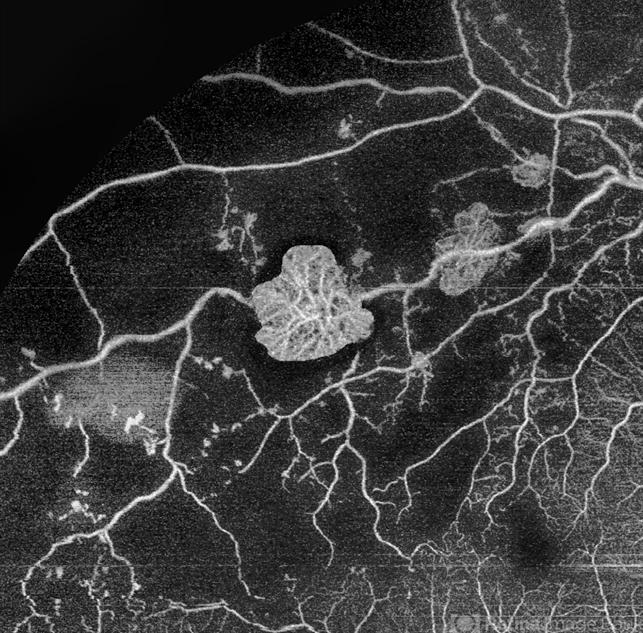

- branch retinal vein occlusion (BRVO), non-perfused branch retinal vein occlusion (BRVO), ST BRVO, non-perfusion, capillary nonperfusion, OCT Angiography, OCT angiography, NVE

- Tufts of NVE's in a case of Branch Retinal Vein Occlusion